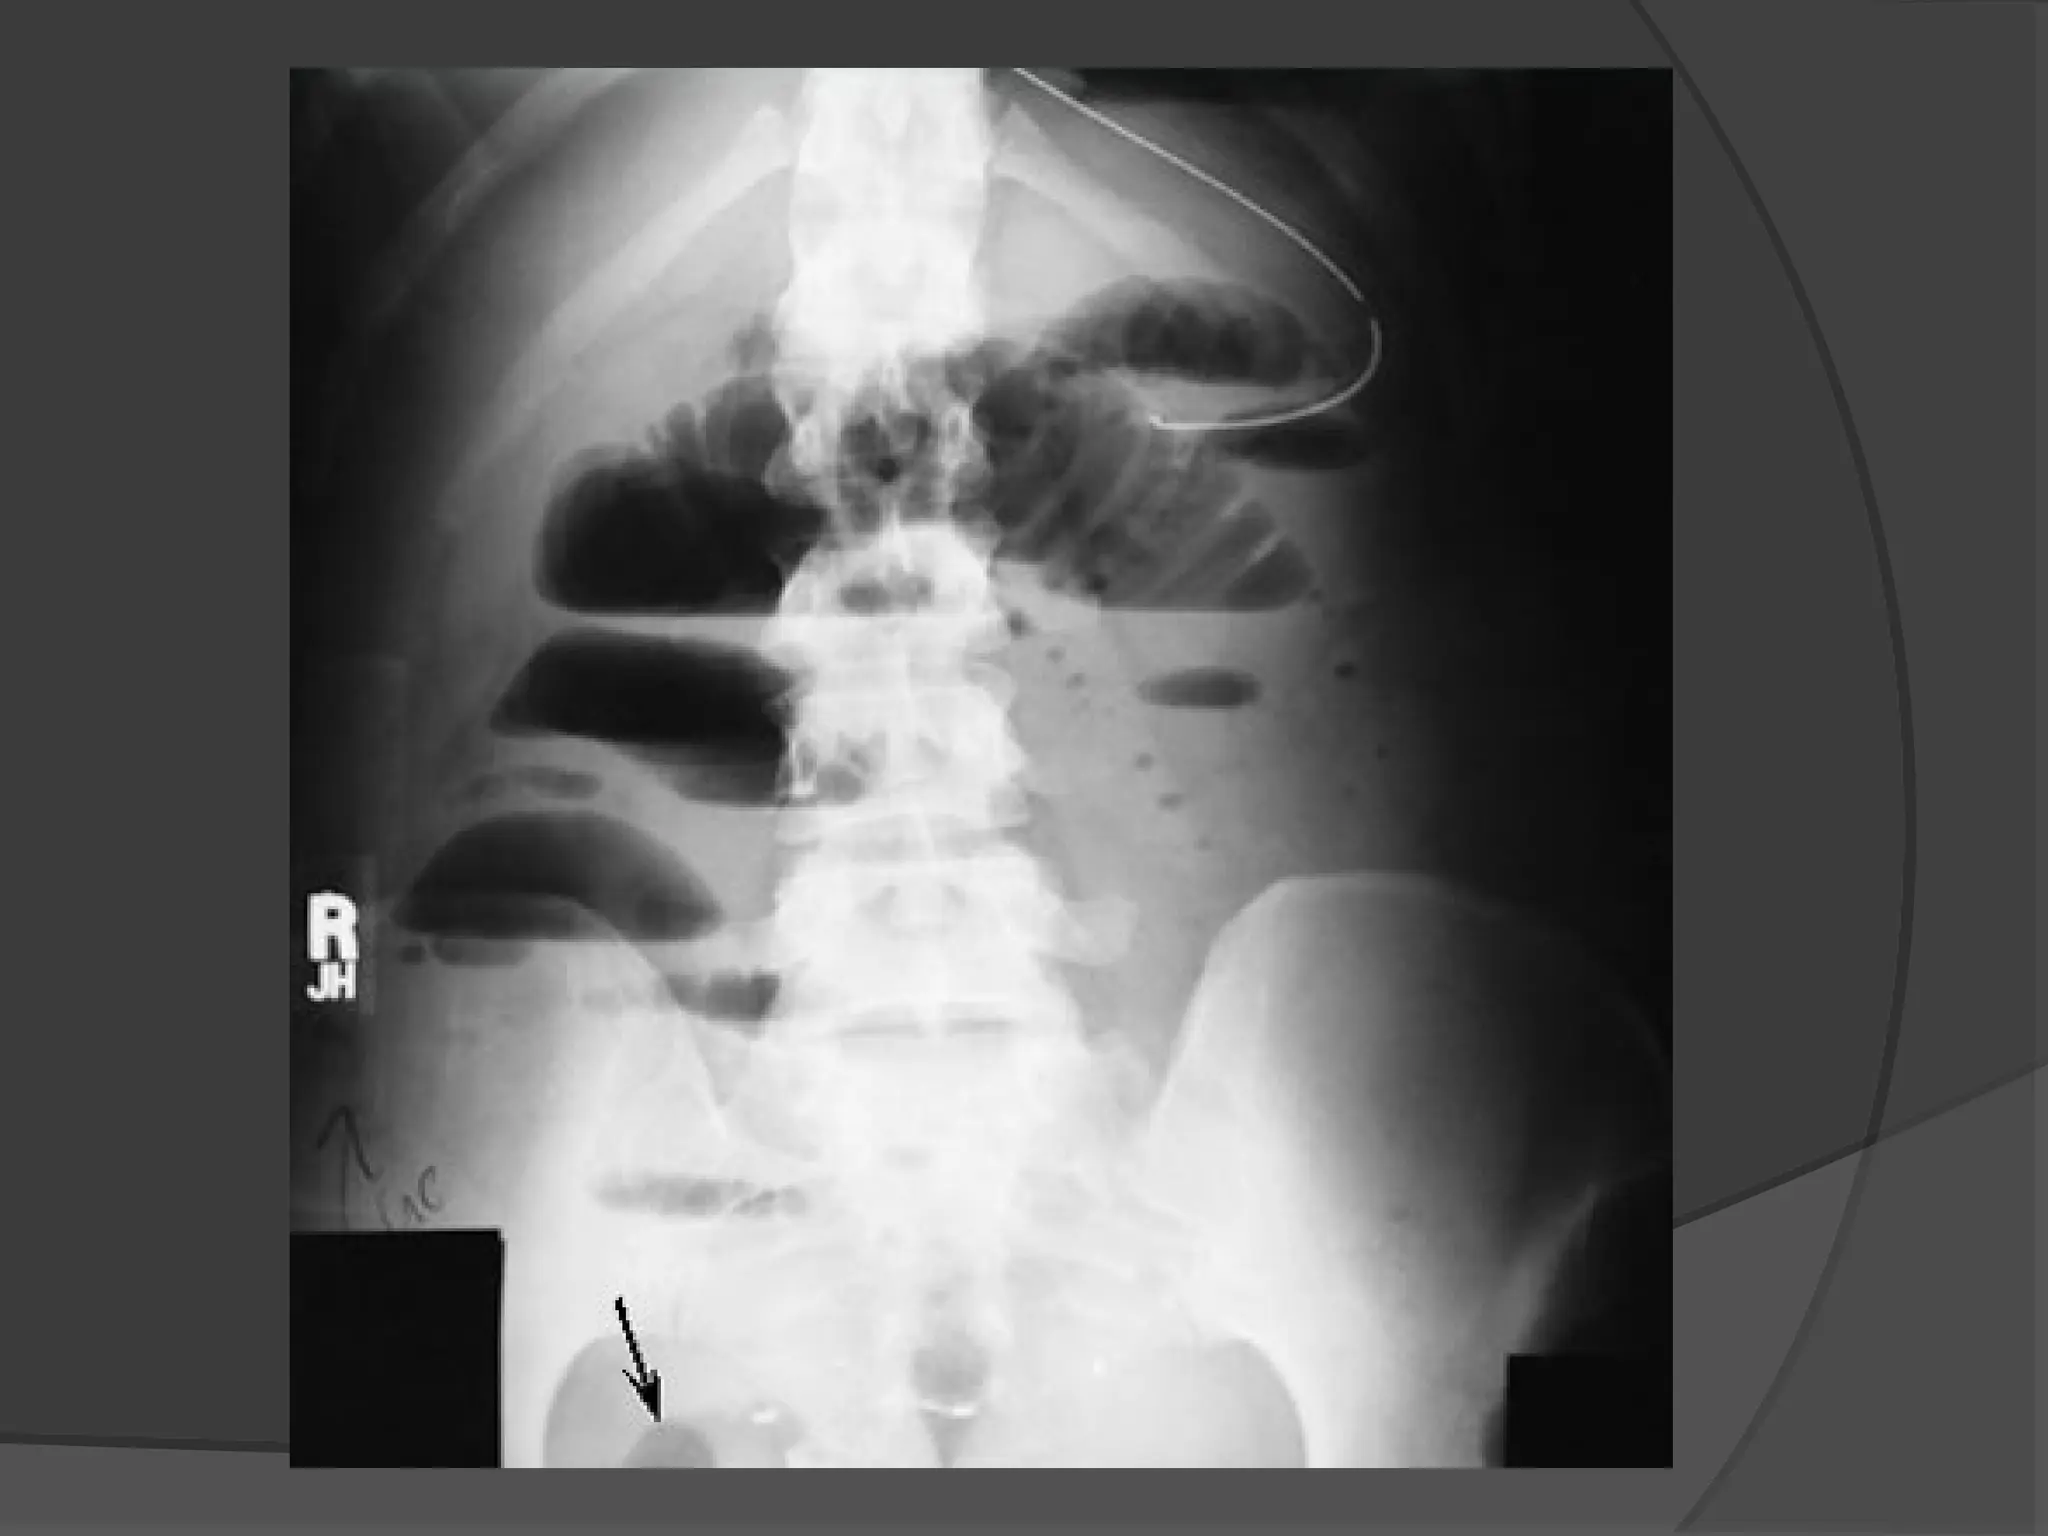

X-RAY

 Distended Large

Bowel Tends to lie

peripherally and to

show the

Hustrations of the

Taenia Coli.

X-RAY- “Barium Follow-Through”

 Patient drinks a contrast medium containing

barium sulfate. Contrast medium appears

white on x-rays, and shows the outline of the

internal lining of the bowel.

 X-ray images are taken at intervals as the

contrast moves through the intestine, (@ 0

minutes→@ 20 minutes→@ 40 minutes →

@90 minutes);

 The bowel is accessed as it becomes visible.

 The test is completed when the Barium is

visualized at the Caecum.